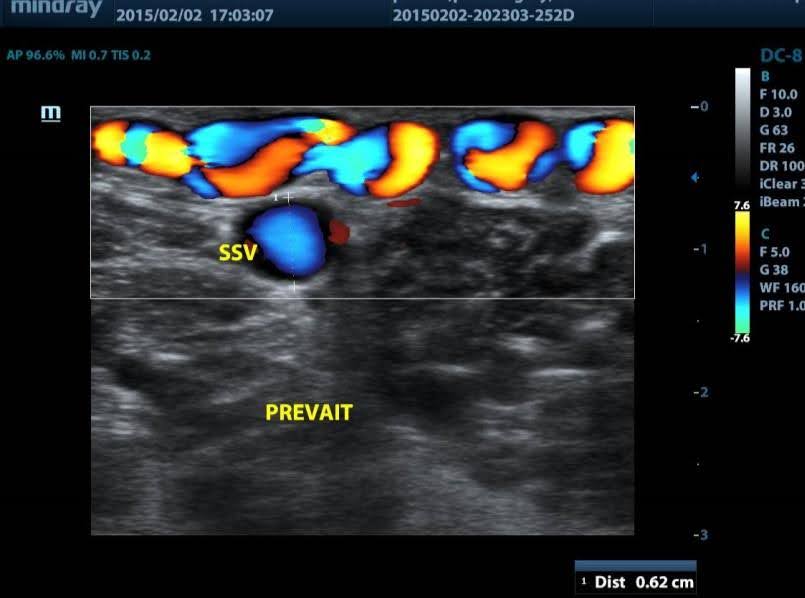

Elle est couramment utilisée en médecine depuis plus d’un siècle, et a bénéficié bien sûr de quelques améliorations techniques. Elle peut se faire sous contrôle de la vue ou sous contrôle écho-Doppler lorsque la varice n’est pas visible sous la peau. Le sclérosant est utilisé sous sa forme liquide initiale, ou peut-être transformé en mousse juste avant injection, pour renforcer son action. Comme pour le laser, la pratique de la sclérothérapie demande une expertise médicale; une formation spécifique est exigée par la Haute Autorité de Santé et par l’Agence du Médicament.

Pour la sclérothérapie, le sclérosant est utilisé sous forme liquide ou sous forme mousse selon le type de varices. Elle peut être guidée par échographie (échosclérothérapie ou sclérothérapie échoguidée) ou non, selon la profondeur et le type de varices.

Le médecin vasculaire va repérer à nouveau en écho-Doppler le réseau variqueux concerné, puis vous serez allongé et selon le type de varice, le geste sera fait soit sous guidage échographique soit sous contrôle de la vue simplement.

Pour renforcer l’efficacité du sclérosant, celui-ci est donc transformé sous forme de mousse en le mixant avec de l’air. La forme mousse permet une meilleure action du sclérosant par une meilleure adhérence à la paroi de la varice, comparée au liquide, et elle bénéficie d’une excellente visibilité en échographie, permettant de mieux sécuriser le geste sous contrôle échographique.